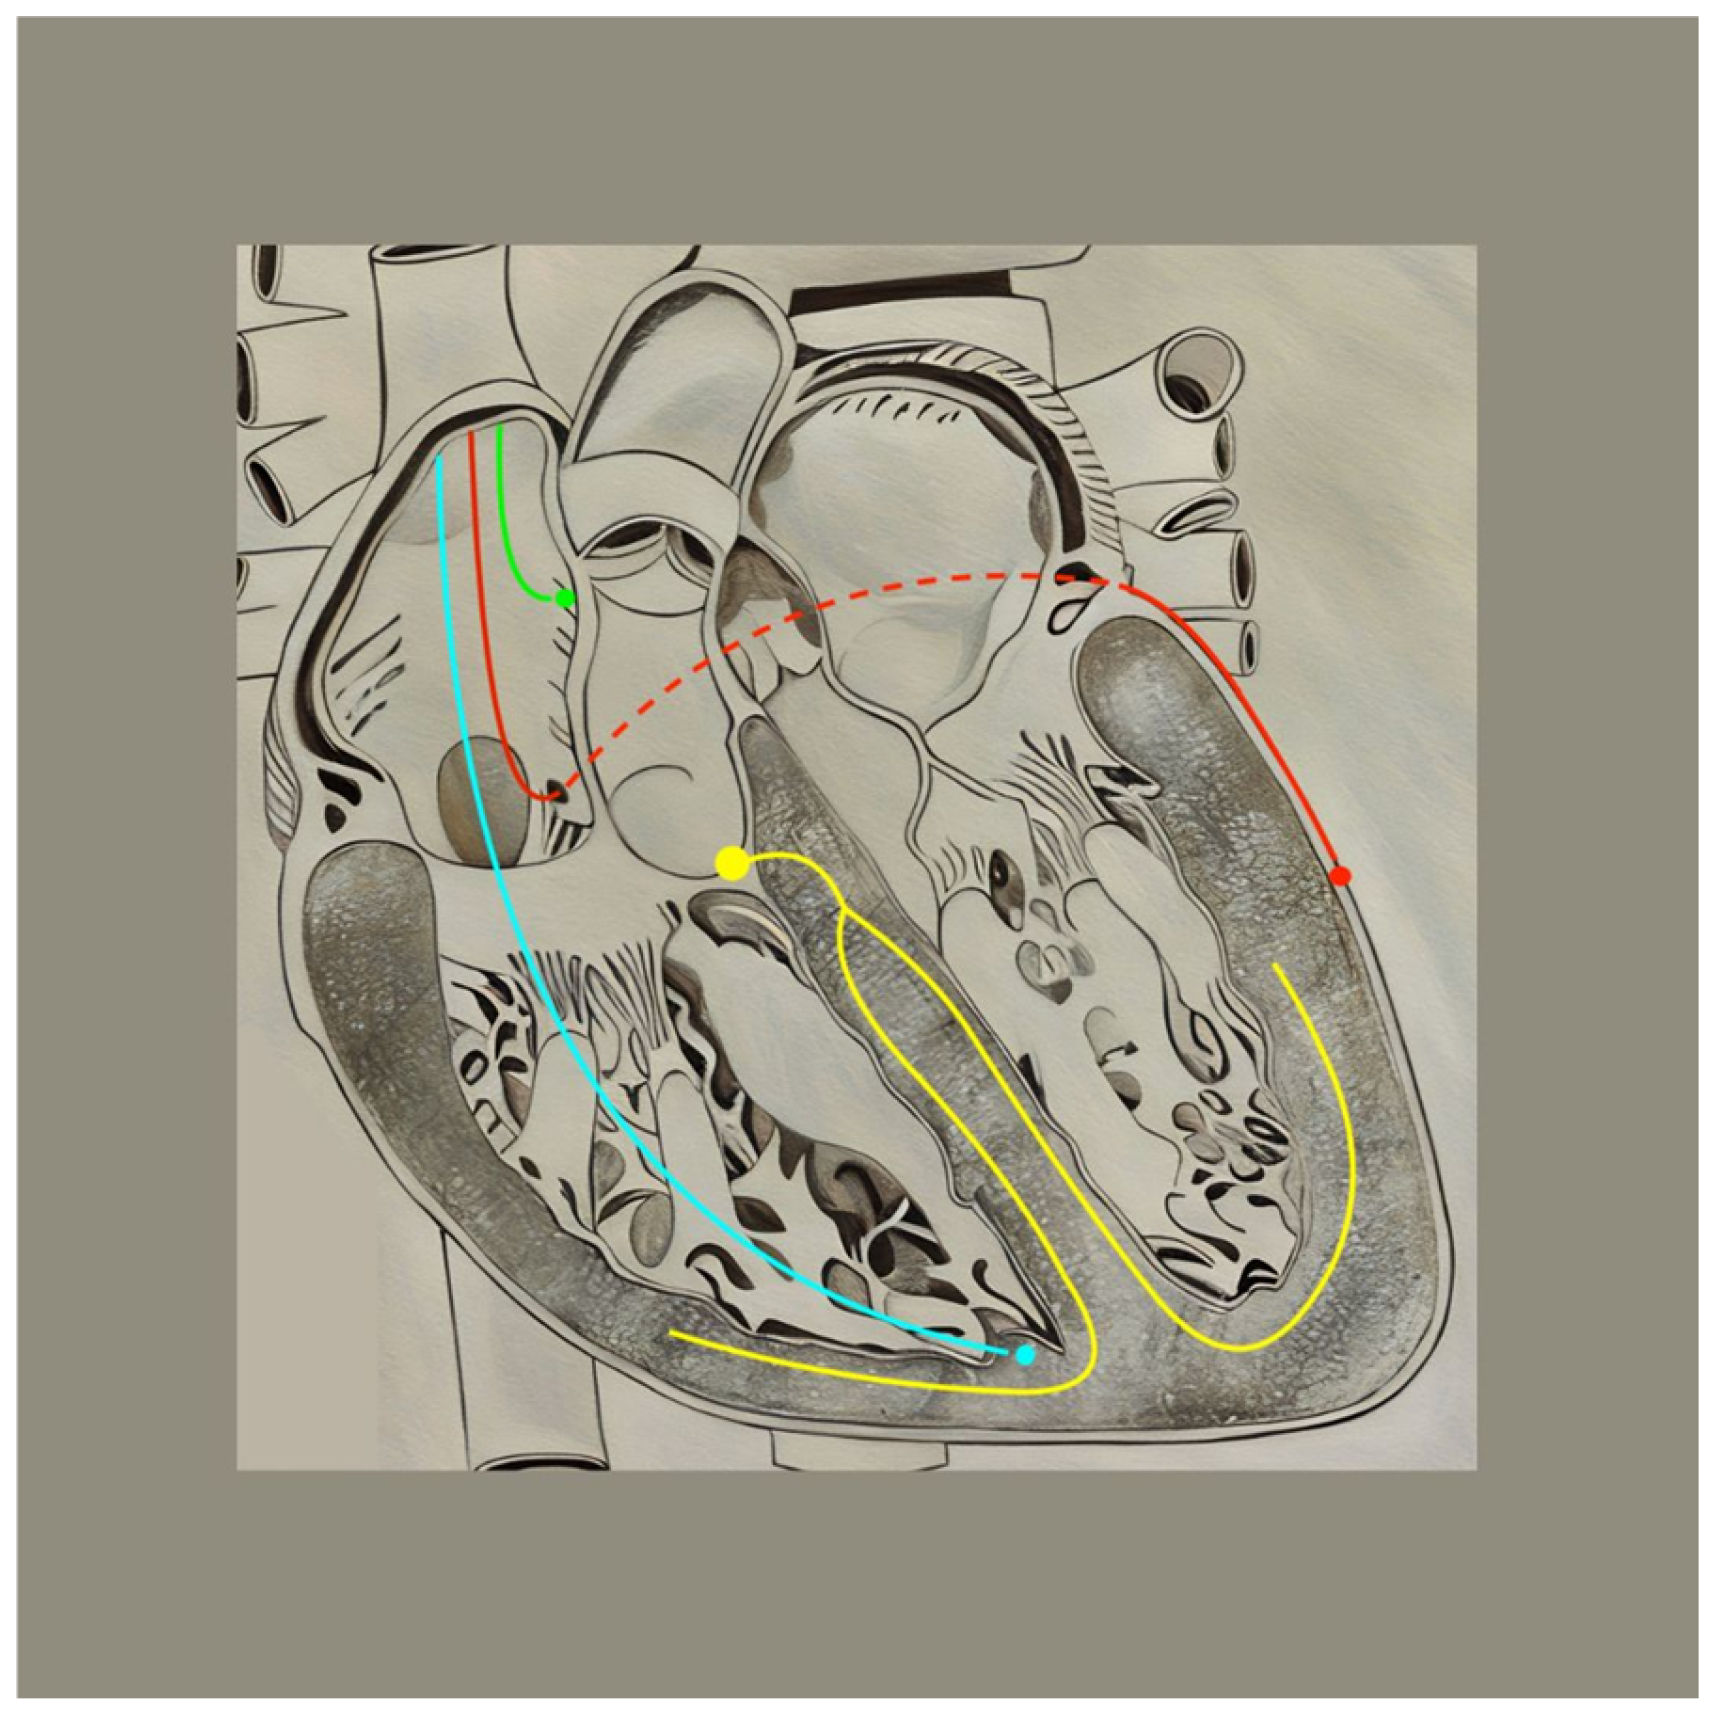

4.1. Biventricular CRT

5.1. His-Bundle Pacing

5.2. Left Bundle Branch Area Pacing

6. A Route Revisited: Endovascular Lead Placement